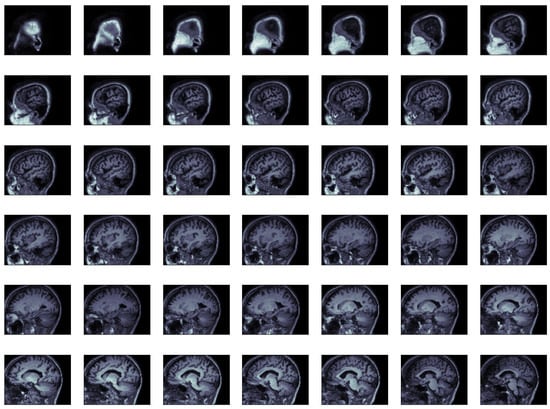

MRI data comprise groups of slices. We present in Figure 1 an extract of the MRI slides of a subject. The extract is not complete. We only show 42 slides out of 170. Each slice is an image, and the combination of images forms the MRI. All images or slices are a pixel matrix. Every slice has an associated spatial thickness because they reproduce reality. Furthermore, all pixels in each slice have a spacing, that is the space they represent. Consequently, the data are volumetric or rectangular cuboids.

Figure 1.

Volumetric data from a subject’s MRI (extracted slice).

In Figure 2, we show an extract of a subject’s processed slices to illustrate these transforms. It is the same subject as in Figure 1. The transform was still volumetric data. The extract is not complete because we only show 42 slices out of 87. As can be seen from the slices, we cut rectangles from the original slices, and these rectangles are compressed, but still show the brain patterns.

Figure 2.

Processed volumetric data from a subject’s MRI (extract of the processed slices).